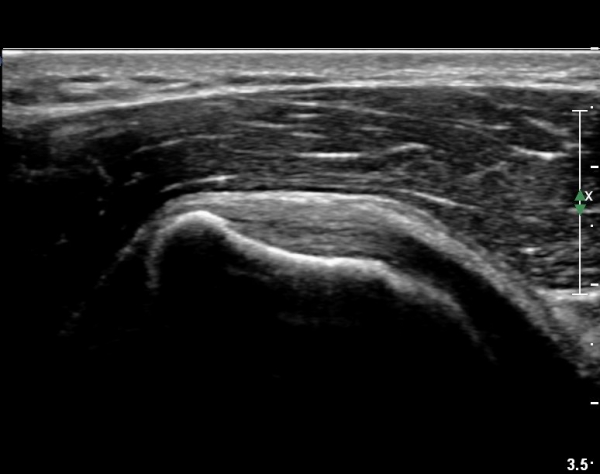

ÃÊÀ½ÆÄ ¼Ò°ß :  ÀÌµÎ¹Ú±Ù°Ç È¾´Ü¸é°Ë»ç¿¡¼­ ¼Ò°áÀý ºÎÂø °ß°©Çϱٰdz» °í¿¡ÄÚ ¼®È¸È­ µ¢¾î¸®°¡ °üÂûµÈ´Ù(»çÁø 1).